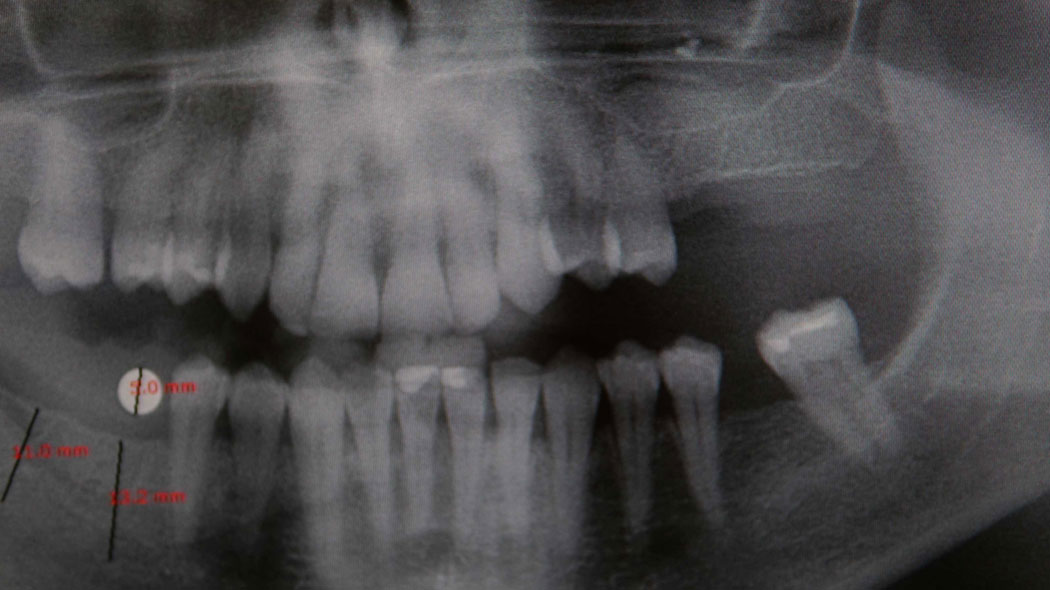

Digitales Röntgen

Ob Kleinbilder einzelner Zähne oder ein Orthopantomogramm (OPG) aller Zähne - die Bilder stehen uns innerhalb kürzester Zeit digital zu Verfügung. Einzelne Aufnahmen können wir bequem für Sie in jedem Zimmer sofort am Stuhl anfertigen.